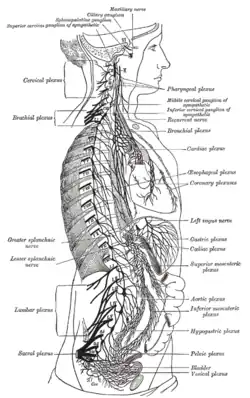

The right sympathetic chain and its connections with the thoracic, abdominal, and pelvic plexuses. (Greater and lesser splanchnic nerves labeled at left.) | |